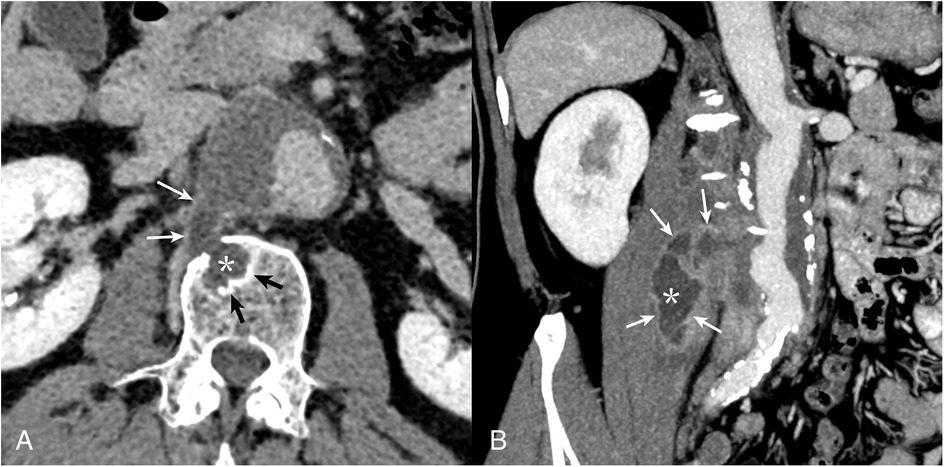

A 65-year-old man was admitted to the vascular surgery department of the Almazov Centre in March 2024 with severe lumbar pain. He had a known thoracoabdominal aortic aneurysm (30 mm since 2020), which had expanded to 50 mm with a para-aortic mass extending to the right m. psoas and right diaphragmatic pedicle, suggesting rupture (Figure 1).

Figure 1

CT angiography of the abdominal aorta. Multiplanar CT reconstructions demonstrate communication of the contents of the vertebral body defect (A), with the cavity of the m. psoas major abscess (B) and the aortic lumen. Borderline (contact) sclerotic changes in the vertebral bodies (black arrows) and late (delayed) accumulation of contrast in the abscess capsule (white arrows) characteristic of the infectious process (asterisk) are noteworthy.